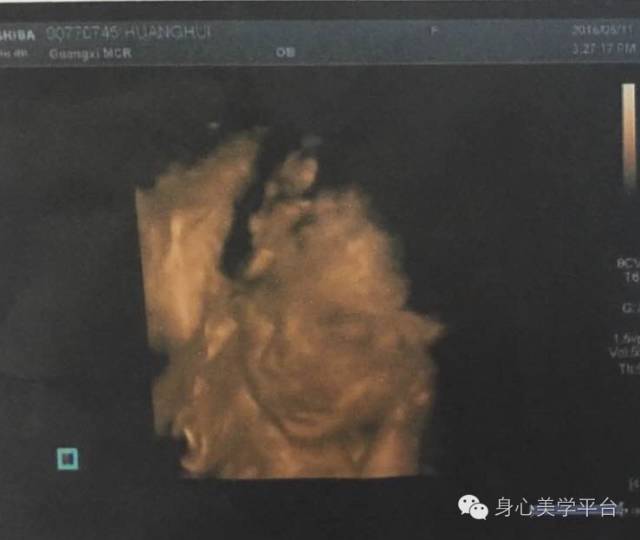

这是我和我老公刚拍的孕照,还有宝宝24周时候的四维彩超,真的很感恩遇见芝华老师。

宝宝真的是跟我在做集体时间限催眠时看到的样子一模一样我两次看到这个样子,太神奇太奇妙了,希望下一次有机会我能与我老公一起参加芝华老师的课程!